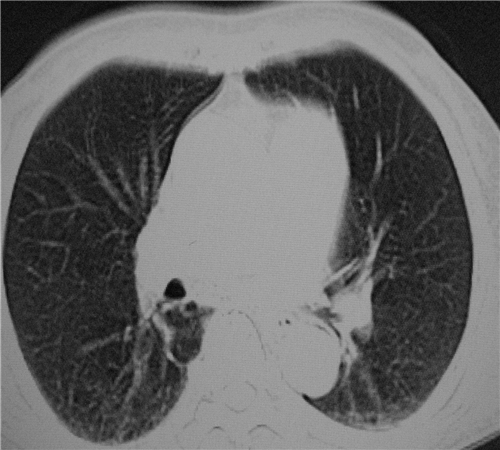

标题: CT26849:女67岁反复胸痛两天余,临床考虑夹层。 [打印本页]

标题: CT26849:女67岁反复胸痛两天余,临床考虑夹层。

右肺感染,未见夹层。

既然考虑夹层,建议强化!另:右下肺感染!

1)右肺感染性病变。2)建议行ct增强扫描或mri检查排除主动脉夹层。

双下肺感染,右侧显著。有无夹层,增强扫描后再诊断。

1. 感染性病变,2.未见夹层,3.食道未见异常。

1.考虑双肺感染,右侧为重;2.建议ct增强或mri排除主动脉夹层

双下肺感染,右侧显著。有无夹层,增强扫描后再诊断。食道未见异常。